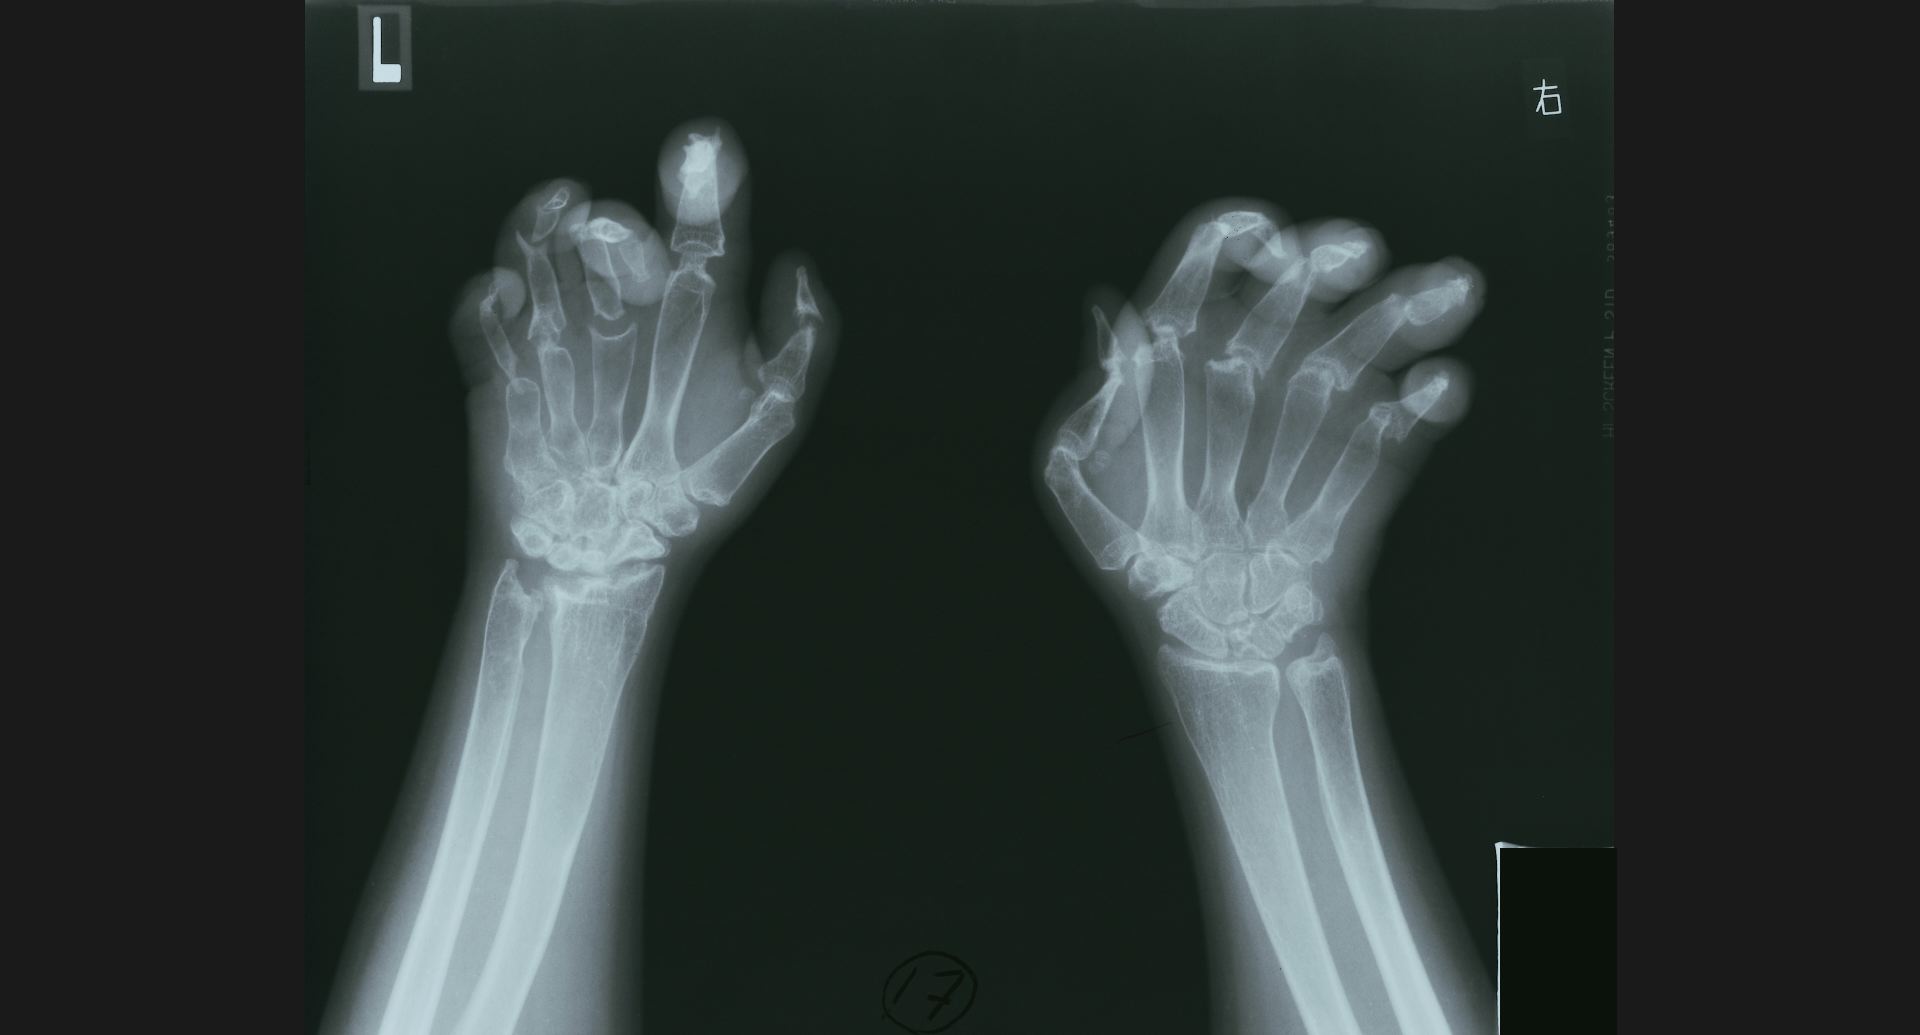

fig.17(81KB) :Acro-osteolysis

radius遠位端の骨梁。骨融解部。